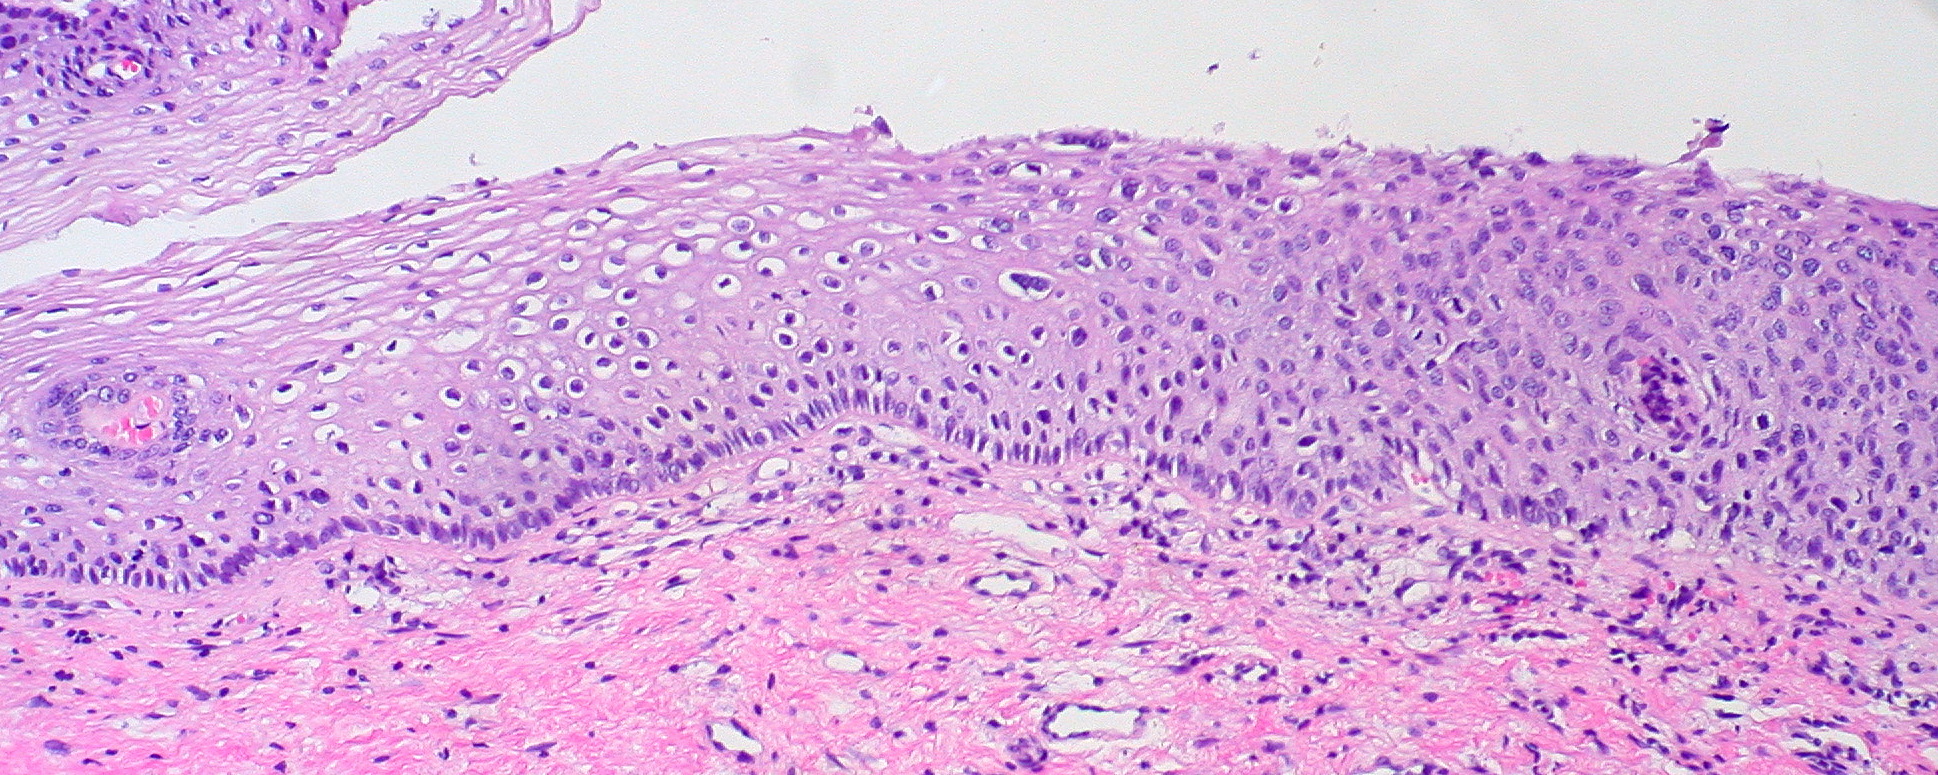

When examined under a microscope, precancerous cervical lesions are classified into three categories based on the extent of abnormal cell growth:

When examined under a microscope, precancerous cervical lesions are classified into one of three categories. These categories depend on how much of the cervix appears abnormal:

When examined under a microscope, precancerous cervical lesions are classified into one of three categories.

These categories depend on how much of the cervix appears abnormal: